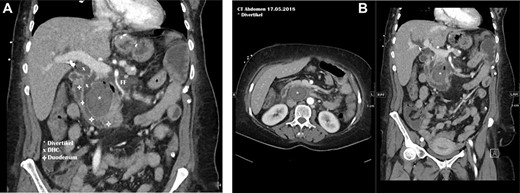

In our emergency department, the patient’s general condition was reduced because of pain and signs of diffuse peritonitis. The vital signs showed a blood pressure of 120/70 mmHg and an accelerated pulse (120 bpm), a respiratory rate of 25/min and a normal body temperature. The blood results showed a leukocytosis with only slightly elevated C-reactive protein (14 mg/l). The CT scan was reviewed and revealed the presence of retroperitoneal and parapancreatic fluid with some air bubbles, which could also be seen in an additional abdominal sonography. Further a thickening of the colon ascendens was found (Fig. 1). A perforated duodenal diverticulum was likely and suspected. The thickening of the ascending colon was interpreted as an accompanying colitis.